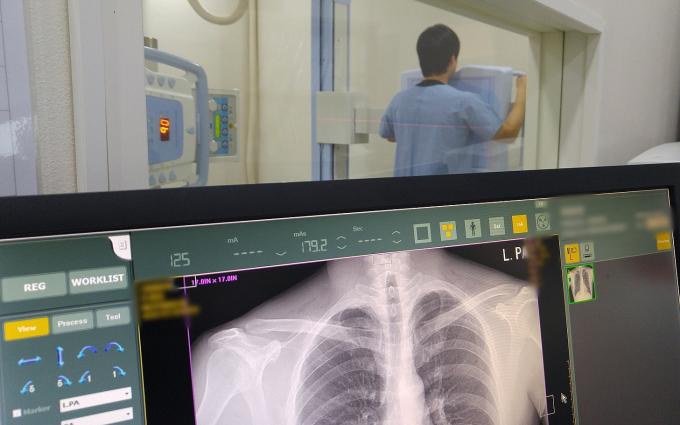

이들은 설문조사와 흉부 X-선 촬영과 의사 진찰 등 기본검진을 거친 뒤, 석면질병 소견이 있는 경우 양산부산대병원에서 2차 정밀검진을 받게 된다.